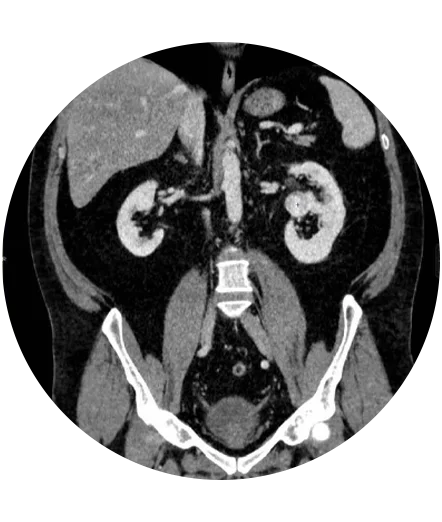

Practicăm urologia modernă care folosește tehnici și proceduri medicale avansate pentru diagnosticarea și tratamentul afecțiunilor urologice, proceduri care sunt actualizate continuu.

Urologia modernă se bazează pe tehnici avansate și inovatoare pentru a oferi tratamente eficiente și personalizate.